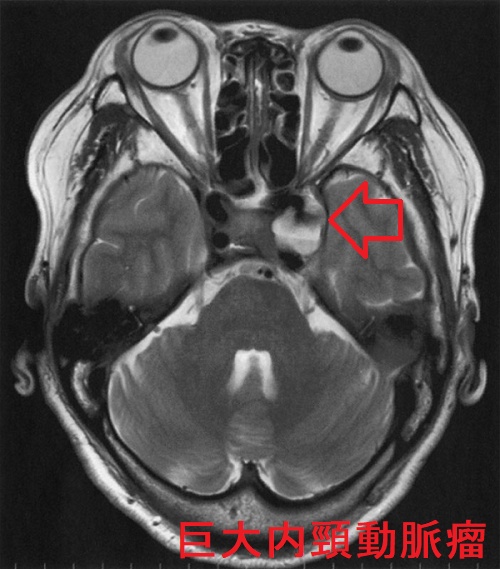

内頸動脈瘤

内頸動脈瘤も内頸動脈-後交通動脈分岐部動脈瘤(IC-PC 動脈瘤)と同じく、動眼神経麻痺を起こします。さらには、滑車神経・外転神経麻痺による複視や三叉神経第1枝・第2枝の圧迫による顔面の知覚障害を伴う場合も。

内頸動脈瘤が破裂した場合、海綿静脈洞内に血液が流れ込むので、くも膜下出血に至りません。しかし、海綿静脈洞内の静脈圧が上昇し、上眼静脈へ逆流するため、眼球突出を来します。ただし、拍動する眼球突出なので、甲状腺眼症(バセドウ病眼症・橋本病眼症)と異なります。